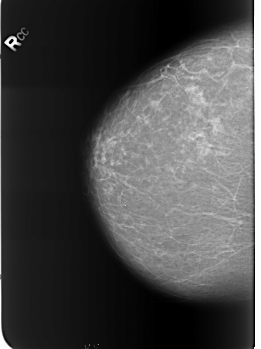

Digital Database for Screening Mammography

Volume: benign_without_callback_01 Case: B-3253-1

B_3253_1.RIGHT_CC

filename B-3253-1

DATE_OF_STUDY 11 8 1998

PATIENT_AGE 61

FILM_TYPE REGULAR

DENSITY 2

DIGITIZER LUMISYS LASER

RIGHT_CC LINES 5576 PIXELS_PER_LINE 4176 BITS_PER_PIXEL 12 RESOLUTION 50 NON_OVERLAY